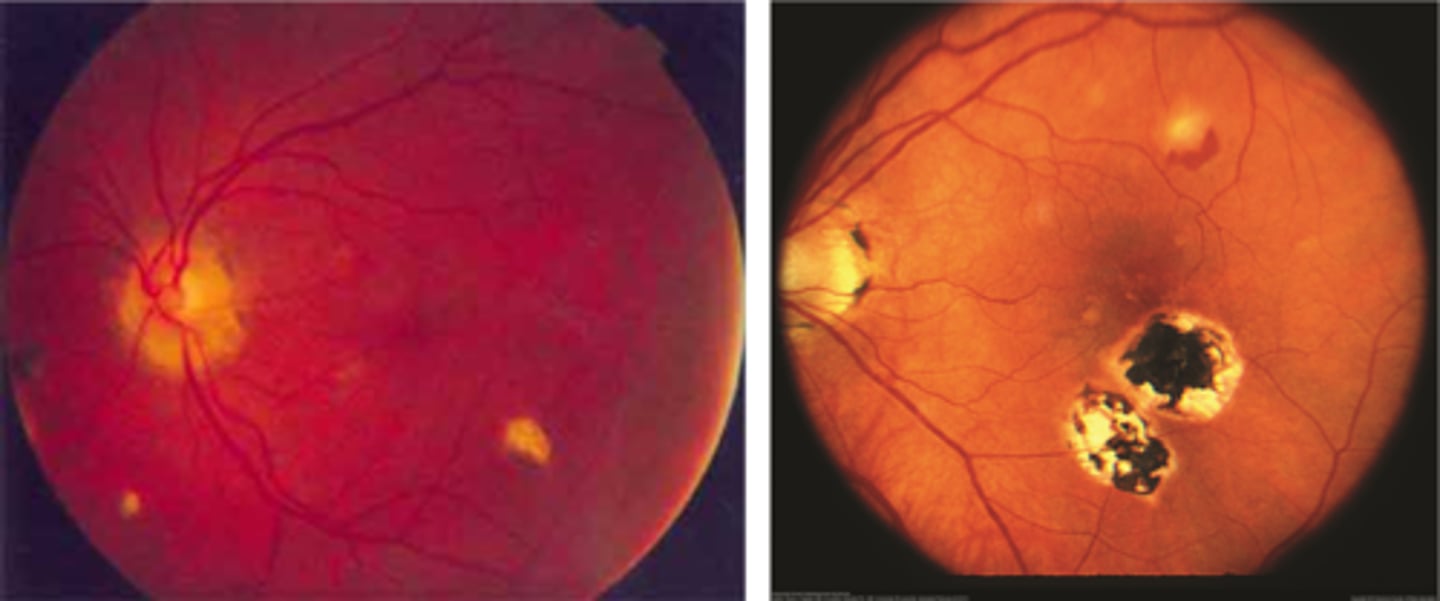

What finding of toxoplasmosis is seen in A/B?

retinitis turns into hazy scar with nerve pallor

What finding of toxoplasmosis is seen in C/D?

scarring overtime with VA loss/scotoma